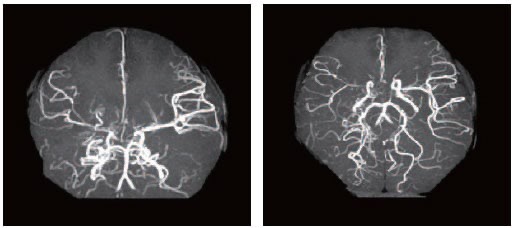

모야모야병은 뇌혈관, 특히 뇌로 혈액을 공급하는 내경동맥과 그 주변 주요 혈관이 점점 좁아지고 막히는 희귀 난치성 질환으로, 혈류가 줄어든 뇌는 부족한 혈액을 보충하기 위해 가느다란 미세측부혈관들을 새로 만들어냅니다. 이 작은 혈관들이 연기처럼 보인다고 하여 일본어로 ‘모야모야(안개·연기)’라는 이름이 붙었습니다. 소아부터 성인까지 폭넓게 나타나며, 특히 5~10세 어린이와 30대 전후의 여성에서 비교적 많이 발견되는 경향이 있습니다. 증상은 일시적 마비, 언어장애, 두통, 실신, 경련 등 매우 다양해 뇌졸중과 유사하거나 초기에는 가벼운 신경학적 증상으로만 나타나 진단이 늦어지기도 했습니다. 질환이 진행하면 허혈성 뇌졸중(뇌경색)이나 출혈성 뇌졸중 위험이 증가하여 반드시 전문적인 관리가 필요합니다. 아직 완전히 예방할 수 있는 방법은 없지만 조기 진단과 적절한 치료를 통해 뇌 기능을 보호하고 삶의 질을 유지할 수 있습니다.

모야모야병은 뇌기저부의 주요 혈관이 서서히 협착되고 막히면서 뇌혈류가 감소하는 만성 진행성 뇌혈관 질환입니다. 협착이 진행된 부위를 대신해 뇌는 생존을 위해 얇고 약한 혈관망을 만들어 혈류를 보충하려 하고, 이 새로운 혈관들이 촬영 영상에서 연기처럼 퍼져 보인다고 하여 ‘모야모야’라는 이름이 붙었습니다. 기전적으로는 내경동맥 말단부와 중대뇌동맥·전대뇌동맥의 기시부에 병변이 가장 잘 생기며, 시간이 지남에 따라 양쪽에 대칭적으로 나타나는 특징을 보였습니다. 이 질환은 단순한 혈관 협착이 아니라 진행성 변화이기 때문에 치료하지 않으면 혈류 부족이 심해지고 뇌 손상이 누적될 수 있습니다. 또한 뇌기능이 체력·호흡·체온 변화 등에 민감하게 반응하기 때문에 과호흡, 울음, 격렬한 운동, 감염 등으로 증상이 악화될 수 있습니다. 즉, 모야모야병은 시간이 지나면서 뇌혈류를 감소시키고 뇌졸중 위험을 높이는 질환이며, 평생 관리가 필요한 만성적 특성을 갖고 있습니다.